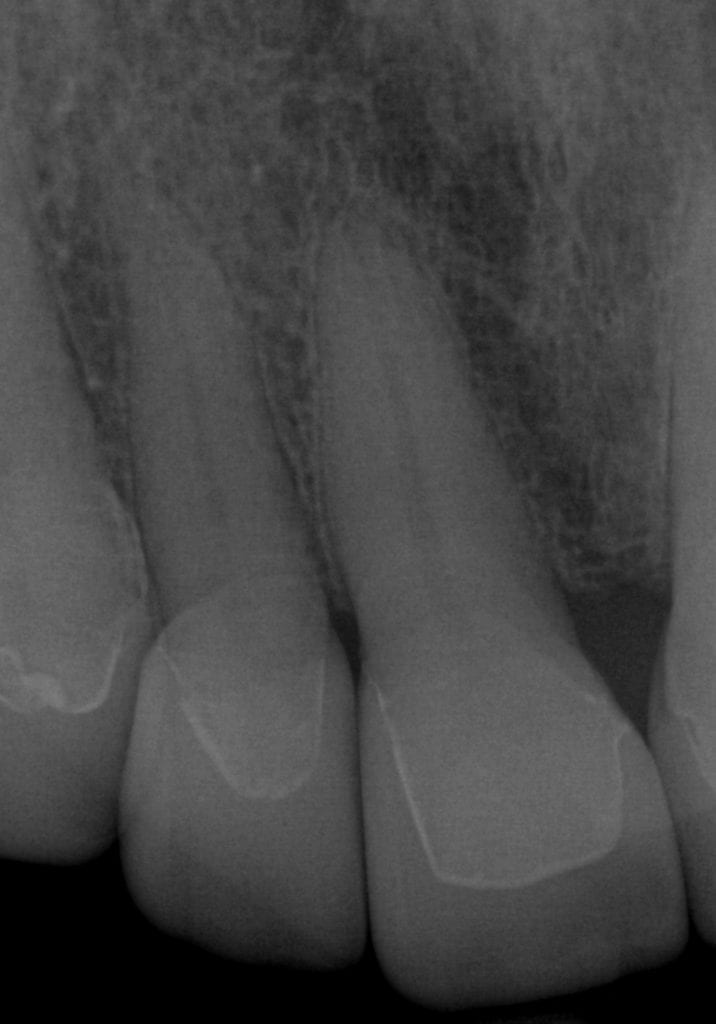

ONE WEEK POST-OP RADIOGRAPHS / CEMENT CHECK